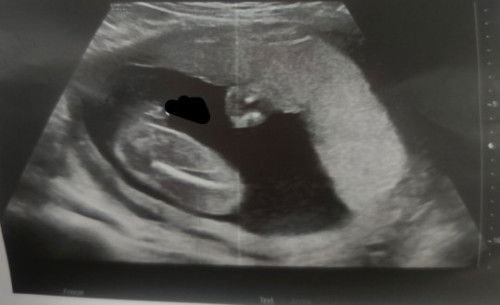

Gender Reveal pahula po

PAGUESS po ng gender ni baby. 🥰😂 Kanina lang po nag ultrasound hehehee thankyou